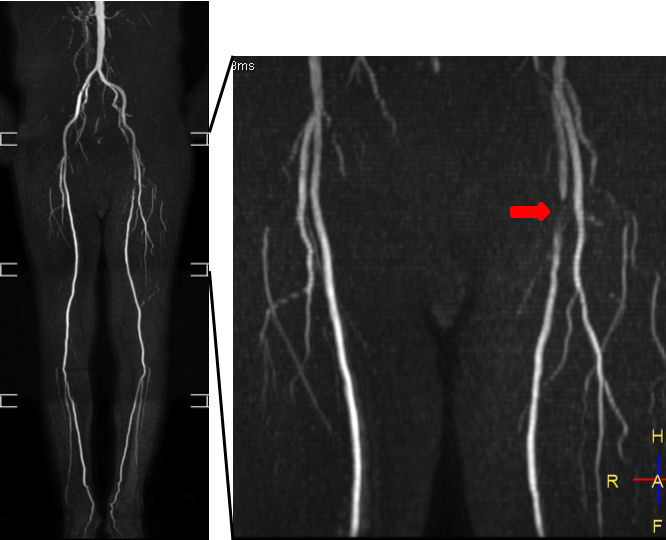

非造影下肢動脈 MRA

非造影下肢動脈 MRA:造影剤を使用せずに腹部から下肢動脈が描出されており,左浅大腿動脈に狭窄(矢印)を認めます。